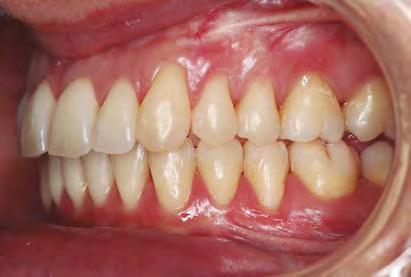

—Al contrario de lo que puede creerse, y pese a que las ventajas de la Ortodoncia invisible suelen asociarse a la Estética, este sistema está también diseñado para afrontar casos complejos. ¿Cuáles destacaría? ¿Y qué beneficios aporta con respecto a la Ortodoncia tradicional?

—Yo, al igual que otros muchos compañeros, nos interesamos en los años 90 por una técnica como la Ortodoncia lingual como respuesta a las necesidades y requerimientos de nuestros pacientes, que entonces era considerada como la auténtica Ortodoncia invisible frente a los brackets estéticos ya existentes en aquel momento.

La verdad es que entonces pensábamos que esta Ortodoncia lingual podía dar las mismas

soluciones que la técnica vestibular, cumpliendo con las exigencias de estética e invisibilidad. Con la aparición de la Ortodoncia plástica hemos visto cómo, en primer lugar, y lo digo por experiencia personal, los mismos pacientes han ido demandándola en sustitución de los brackets estéticos y de los linguales. En mi caso, al igual que otros muchos compañeros, seguimos trabajando con ambas técnicas, pero también es cierto que, en la medida en que los alineadores han dado un mayor grado de corrección y predictibilidad, ha aumentado de forma ostensible su uso y aplicabilidad incluso en casos muy complejos pudiendo decir que, al igual que ocurre con las otras técnicas, cada vez son menos los casos que no podríamos abordar con su empleo.

—El hecho de que el tiempo de tratamiento con los alineadores sea similar o incluso inferior al tratamiento con brackets, además de otras ventajas como que estos aparatos son removibles y, por lo tanto, la higiene bucal es más sencilla y el riesgo de caries disminuye; que son más confortables por ser lisos y adaptarse perfectamente a los contornos de los dientes evitando rozaduras o llagas, así como urgencias; y, en último término, que sean muy estéticos por su transparencia dando una sensación de casi invisibilidad, han hecho que el paciente los aprecie de una forma especial, aunque tenemos que saber que hay limitaciones en el tratamiento de determinadas maloclusiones y tratamientos en los que los brackets son los recomendados.

Francamente, no creo que los brackets puedan ser sustituidos en todas sus facetas y aplicaciones, tanto en cuanto que determinados principios biomecánicos no son aplicables con la misma precisión y fiabilidad con los alineadores.